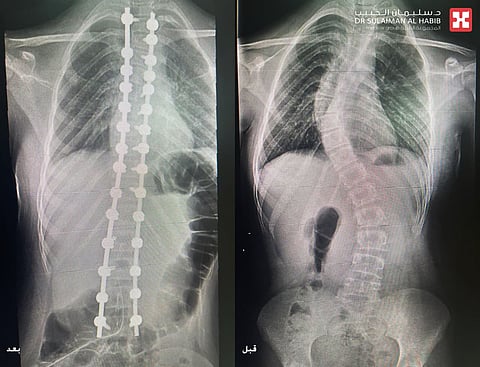

أجرى مجمع الدكتور سليمان الحبيب الطبي بالعليا، عملية جراحية دقيقة لإنهاء معاناة فتاة تبلغ من العمر 13 عاماً، تعاني من إنحناء وجنف مضاعف بالعمود الفقري تبلغ زاويته 70 و45 درجة على التوالي، وذلك عن طريق استخدام تقنيات الذكاء الاصطناعي (AI) والطباعة ثلاثية الأبعاد (3D). ذكر ذلك الدكتور عوض العوض استشاري جراحة العظام والعمود الفقري، رئيس الفريق الطبي المعالج الحاصل على الزمالة الأمريكية والسويدية.

مفيداً بأنه تم اخضاعها لعدد من الفحوصات الطبية الدقيقة بالتصوير المقطعي (C.T Scan)، والأشعة السينية الرقمية (Digital X-Rays)، والرنين المغناطيسي (M.R.I) والتحاليل المخبرية، والتي كشفت بدقة أن الفتاة تعاني من جنف مُضاعف في منطقة فقرات الصدر والفقرات القطنية بزاوية انحراف كبيرة، فضلاً عن وجود إنحراف تعويضي في منطقة التقاء الفقرات الصدرية مع العنقية بنسبة 30 درجة. مشيراً إلى أن هذا النوع من الإعوجاج يُعد من حالات الجنف شديدة التعقيد.

وقد استغرقت العملية قرابة الثلاث ساعات تحت التخدير العام، وتم فيها تعديل فقرات العمود الفقري بدقة عالية، نقلت بعدها المراجعة إلى جناح التنويم، مشيراً إلى أن نتائج الفحوصات ما بعد التدخل الجراحي أكدت نجاح العملية ولله الحمد. وقد بدأت المراجعة في المشي صباح اليوم التالي للعملية، وظهر بوضوح إعتدال العمود الفقري واتزان الأكتاف، وخرجت الفتاة من المستشفى بعد 3 أيام وهي بصحة جيدة .